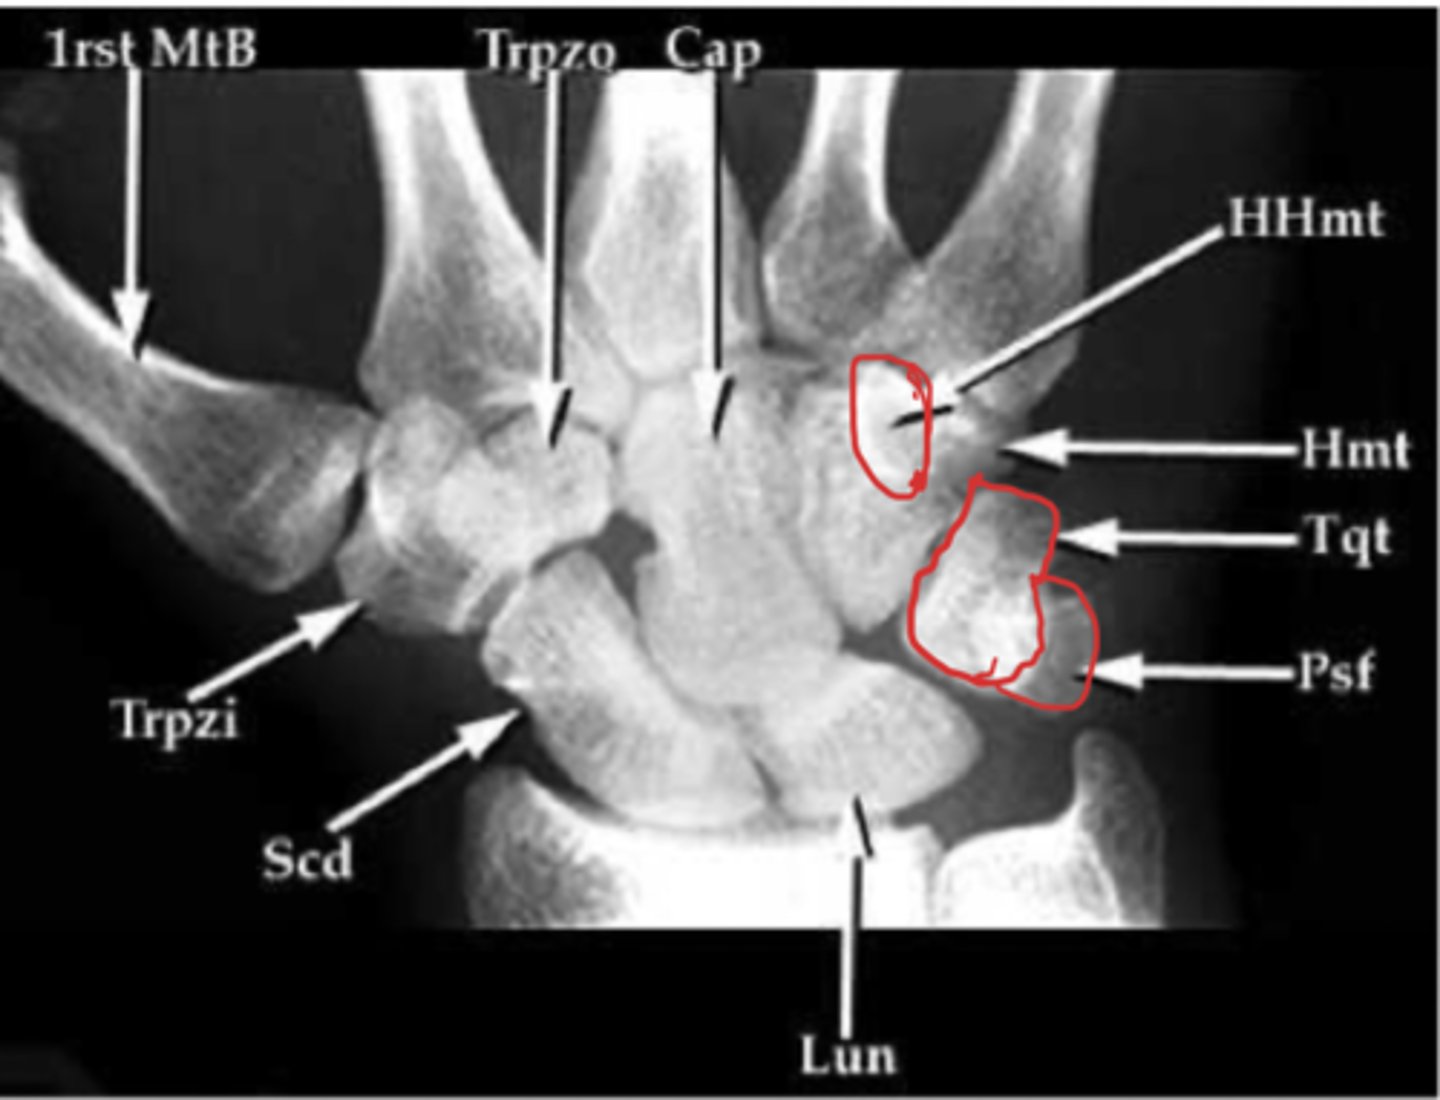

Carpal tunnel view

What view is this?